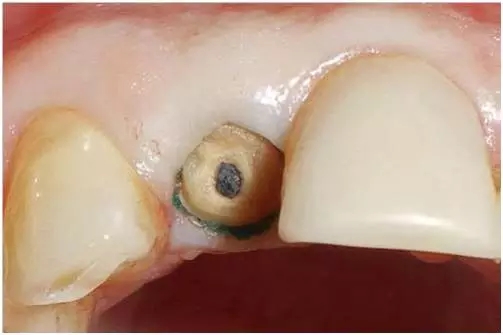

口內(nèi)檢查(圖1至4);

圖4:外傷9天后的臨床檢查:12牙牙冠在釉牙骨質(zhì)界水平處折斷。在使用牙齦收縮線后可以評估整個斷面。